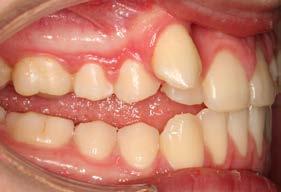

Figura 3. Lateral derecha. Figura 4. Izquierda de inicio. Figura 5. Frente. Figura 6. Overjet, laterales derecha e izquierda.

Las fotografías intraorales muestran las relaciones molares clase II y las relaciones caninas clase II bilaterales (Figura 3 y 4), espaciamiento anterosuperior, un overjet y overbite aumentado (Figura 5). La forma de los arcos es cuadrada, superior e inferior, con el apiñamiento moderado inferior y los espacios en superior.